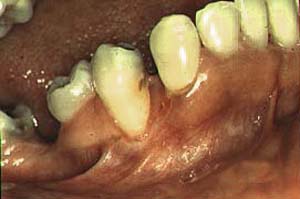

Gingivitis ulceronecrotizante antes del tratamiento local

Post tratamiento con limpieza ultrasónica e irrigación con gluconato de clorhexidine.

La gingivitis ulceronecrotizante aparece con las encías eritematosas y muy inflamadas con áreas de necrosis de las encía marginal y pérdida de las papilas interdentales. se observa en un 5 a 11% de los casos de VIH/SIDA y esta en relación estrecha con el conteo bajo de CD4.

Se han aislado  Borellia y otras espiroquetas, cocos gram positivos, estreptococos hemolíticos y cándida albicans al examen bacteriológico.